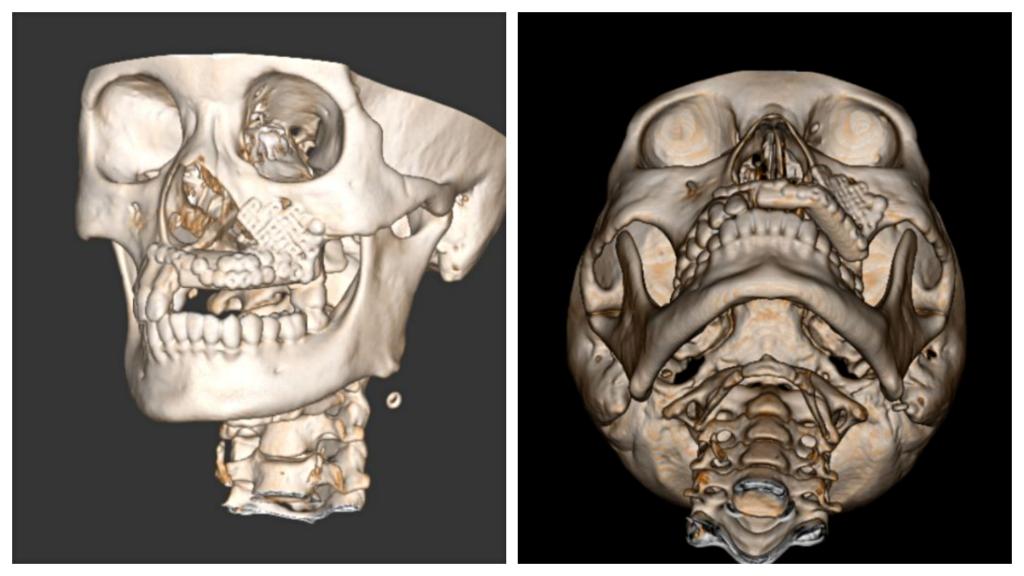

本次手术历时6个小时,吴亚东团队精确切除了患者左上颌骨肿瘤,利用数字化血管化腓骨瓣及个性化钛网重新恢复了这位年轻妈妈的面型及上颌骨缺损。术后在口腔颌面外科护理团队的精心护理下,患者病情恢复良好,现已治愈出院。面型基本对称,移植的腓骨瓣存活良好。半年后,这位年轻的妈妈就可以利用“新的上颌牙槽嵴”进行种植牙恢复咀嚼功能。

目前,口腔医院完成血管化骨瓣移植修复重建下颌骨、血管化肌皮瓣修复软组织缺损已超百例,技术成熟,各类骨肌皮瓣存活率极高。但上颌骨肿瘤因临近鼻腔、上颌窦、眼眶等重要复杂结构,缺损的形态不规则,切除后缺损的修复有极大难度。上颌骨切除术后会导致口鼻瘘、面型畸形、语言及进食障碍、甚至对病人及其家属造成巨大的心理障碍。口腔颌面外科致力于解决患者的病痛,利用计算机辅助设计 / 计算机辅助制造(computer assisted design/computer assisted manufacture,CAD/ CAM),精准切除肿瘤及修复上颌骨缺损。术前设计、术中准确控制以及术后可靠预测,手术可获得理想上颌骨重建效果。在满足患者外形需求的同时,还保障了相关功能,真正做到了个性化功能性修复重建。

手术的成功标志着beat365唯一官方网站附属口腔医院口腔颌面外科修复重建技术已经可以涉及头颈颌面部各区域各类软硬组织缺损,填补了省内上颌骨缺损修复重建的技术空缺。